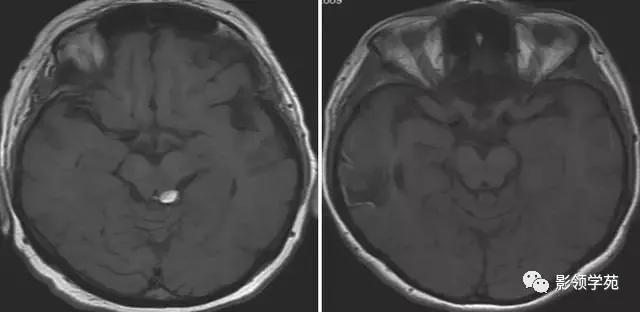

图 2 左图为左侧乙状窦血栓;右图上矢状窦血栓